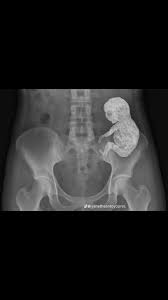

“It’s unusual… but I believe it’s a Lithopedion.”

Lithopedion.

Stone baby.

Sometimes, in very rare cases, a pregnancy develops outside the womb.

The body cannot expel it, and to protect itself, it encases the fetus in calcium, turning it into a hard, stone-like form.

It is a natural defense—a preservation of both life and self—but also a silent witness to something that had occurred decades ago.

Doctors eventually removed the calcified fetus, carefully, with precision and respect.

There it was, preserved in stone, a life that had existed silently alongside hers for decades.